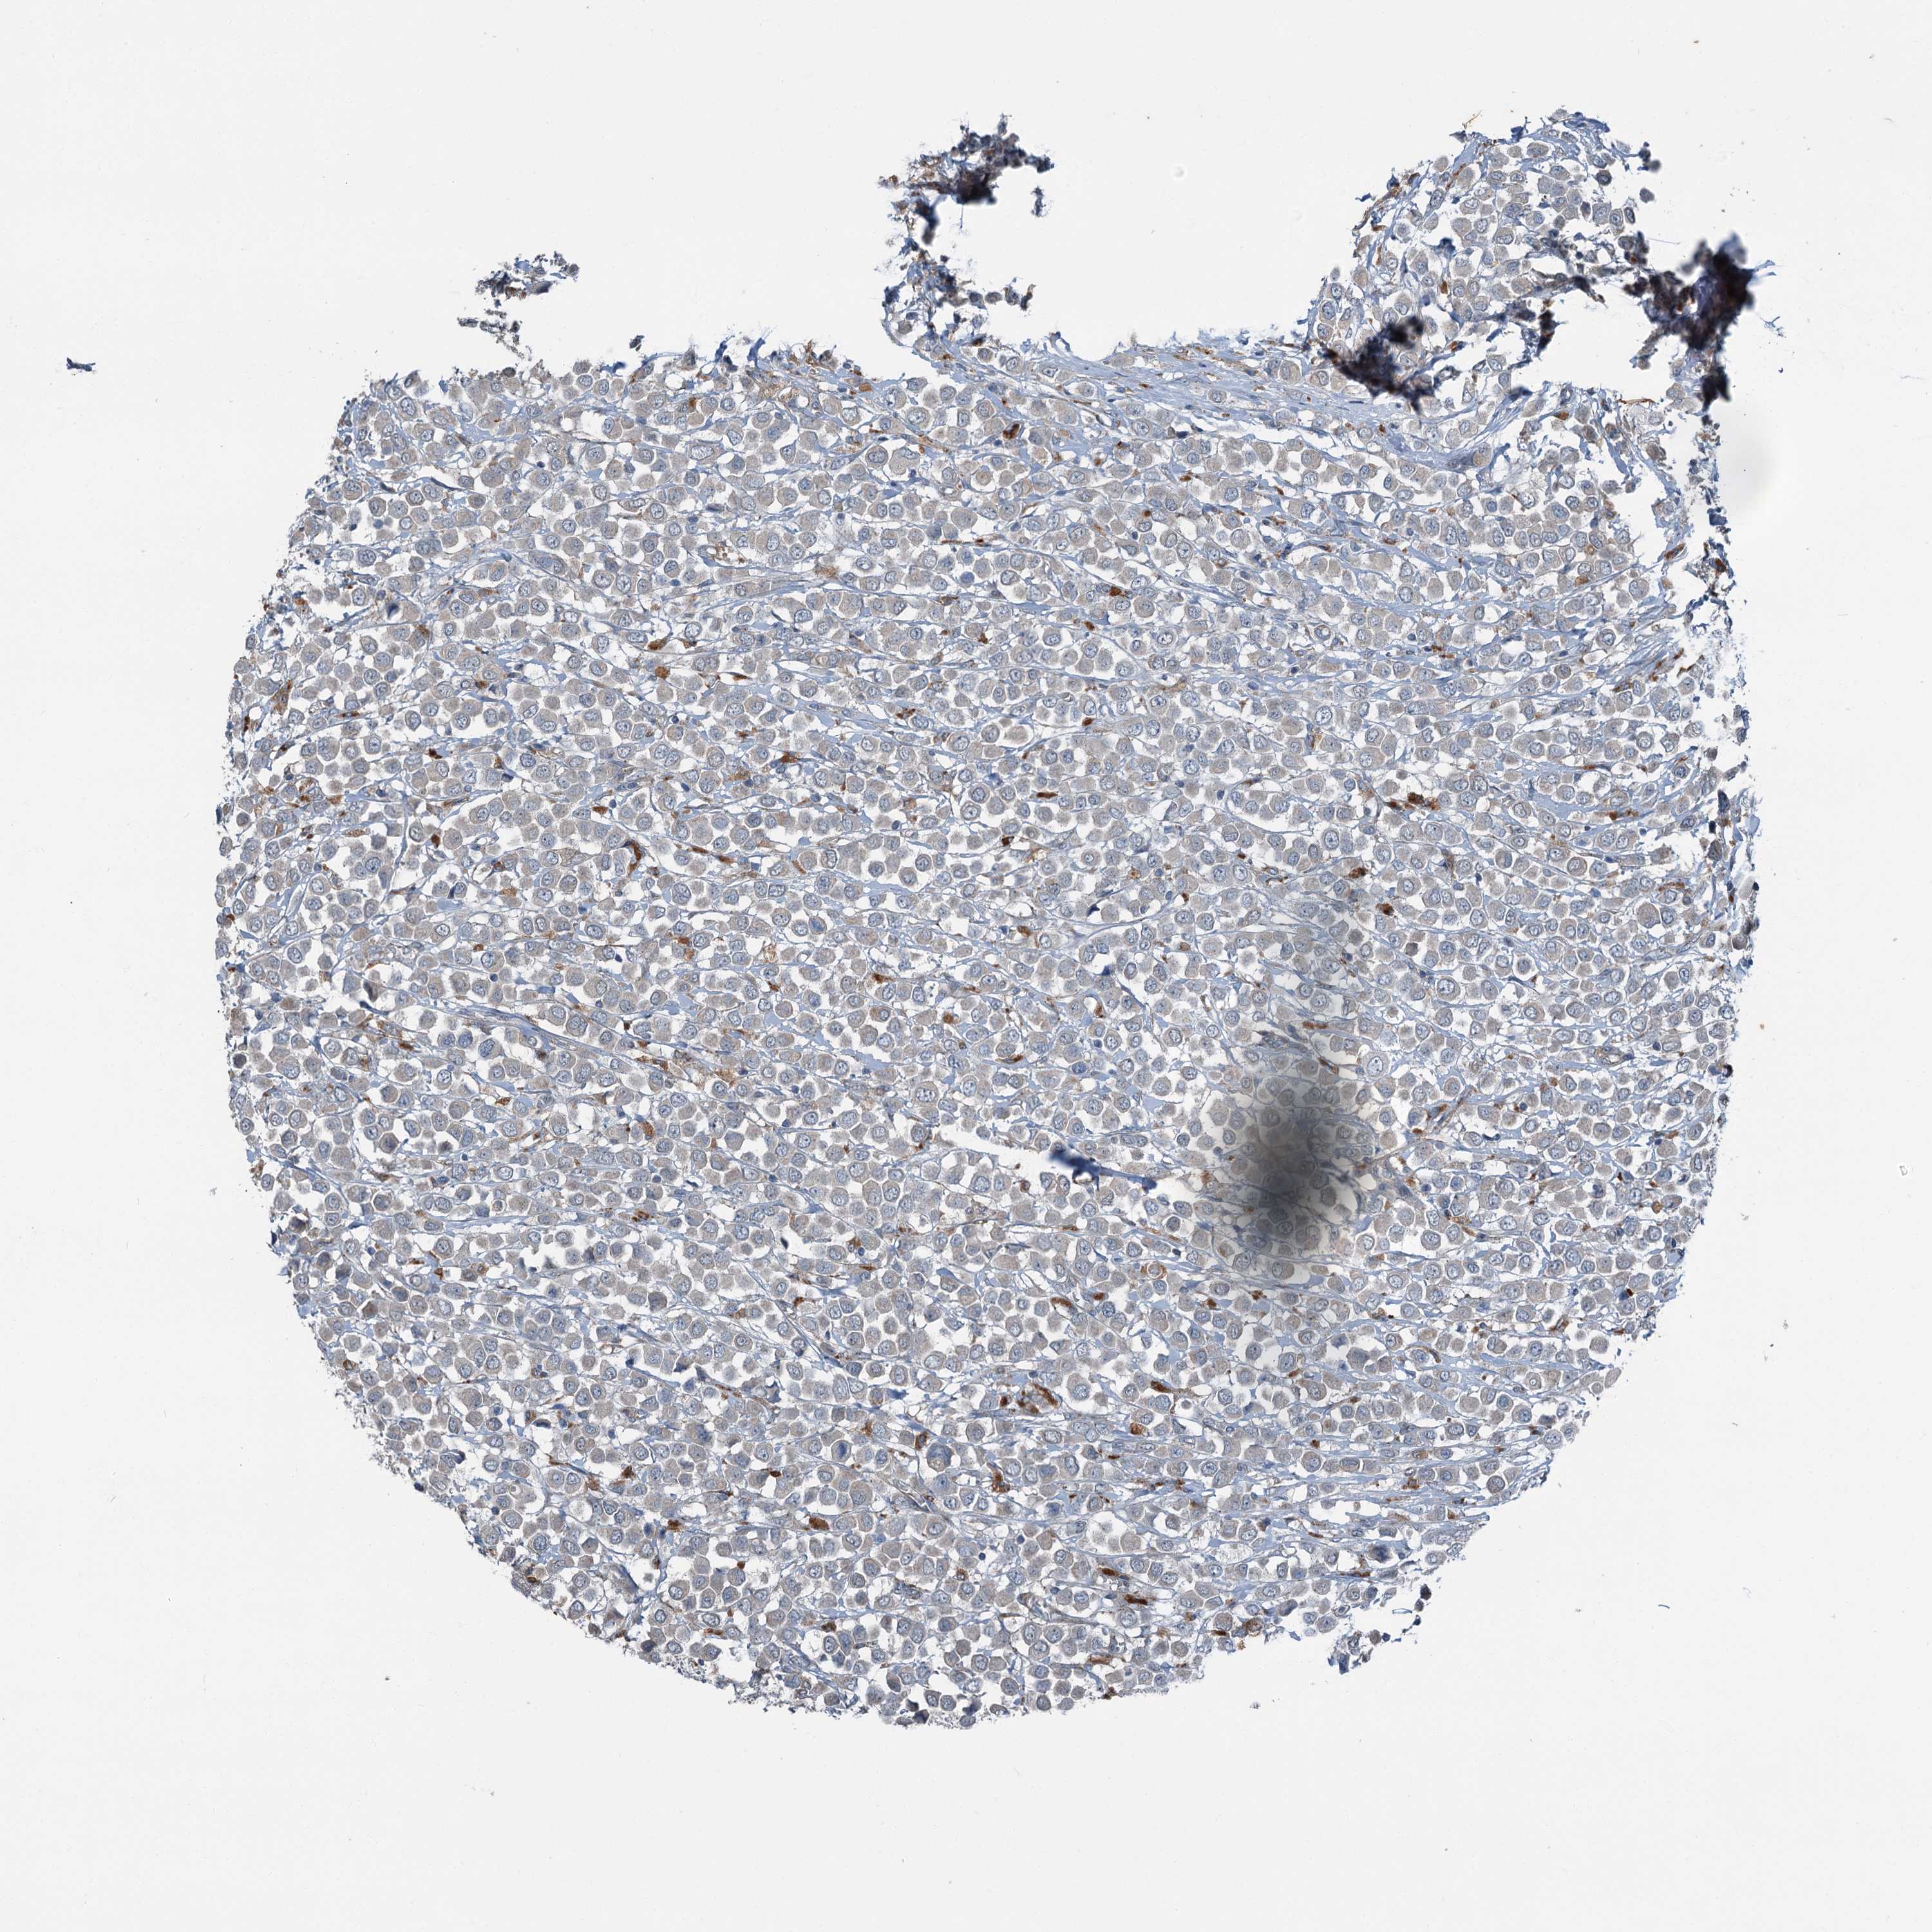

BRCA TCGA BRCA VALIDATION PROTEIN EXPRESSION